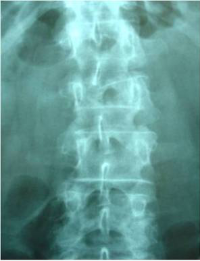

Estabilització percutània de fractures vertebrals inestables

En casos de fractures vertebrals complexes, inestables, comminutes, etc. es requereix una estabilització addicional de la fractura mitjançant una artròdesi percutània, i en alguns casos en els quals hi ha compromís neurològic, una descompressió del canal medul·lar. L’artrodesi percutània permet estabilitzar l’estructura compromesa de la columna vertebral i descarregar la càrrega del pacient sobre la fractura. Addicionalment se solen cementar les vertebres artròdesis i la fractura vertebral mitjançant cifoplastia.

Cas clínic d'una resecció (corpectomia) i reconstrucció vertebral lumbar en una fractura esclat de nivell L4.